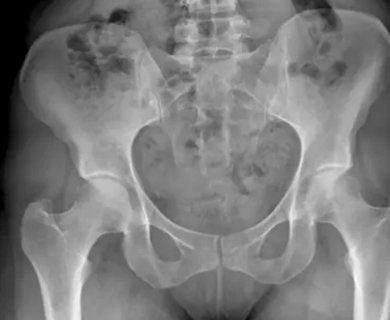

Dysplastic Hips

When the diagnosis of acetabular dysplasia is made, the X-ray may show signs of arthritis which is most commonly an acetabular cyst though increased bone density, a femoral head cyst, osteophytes (bone spurs), and/or cartilage thinning may also be present. Dysplasia with X- ray findings of secondary arthritis have a poorer prognostic outcome.